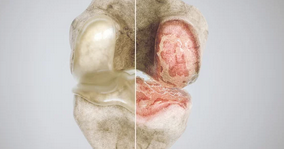

무릎 관절염은 관절 내 연골이 닳거나 손상되면서 통증과 운동 제한이 발생하는 질환이다.

3. 무릎 관절염 진행 단계

무릎 관절염은 초기에는 가벼운 통증과 불편감으로 시작되지만, 점차 진행되면서 무릎 기능이 저하된다.

✅ 무릎 관절염 진행 4단계

✔ 1단계 (초기) – 가벼운 통증, 무릎이 뻣뻣하지만 생활에는 큰 불편 없음

✔ 2단계 (중기) – 계단 오르기 어려움, 오래 걸으면 무릎이 붓고 통증 발생

✔ 3단계 (진행기) – 일상생활 중에도 지속적인 통증, 관절이 붓고 변형 시작

✔ 4단계 (말기) – 연골이 거의 닳아 뼈끼리 마찰, 극심한 통증과 보행 장애 발생